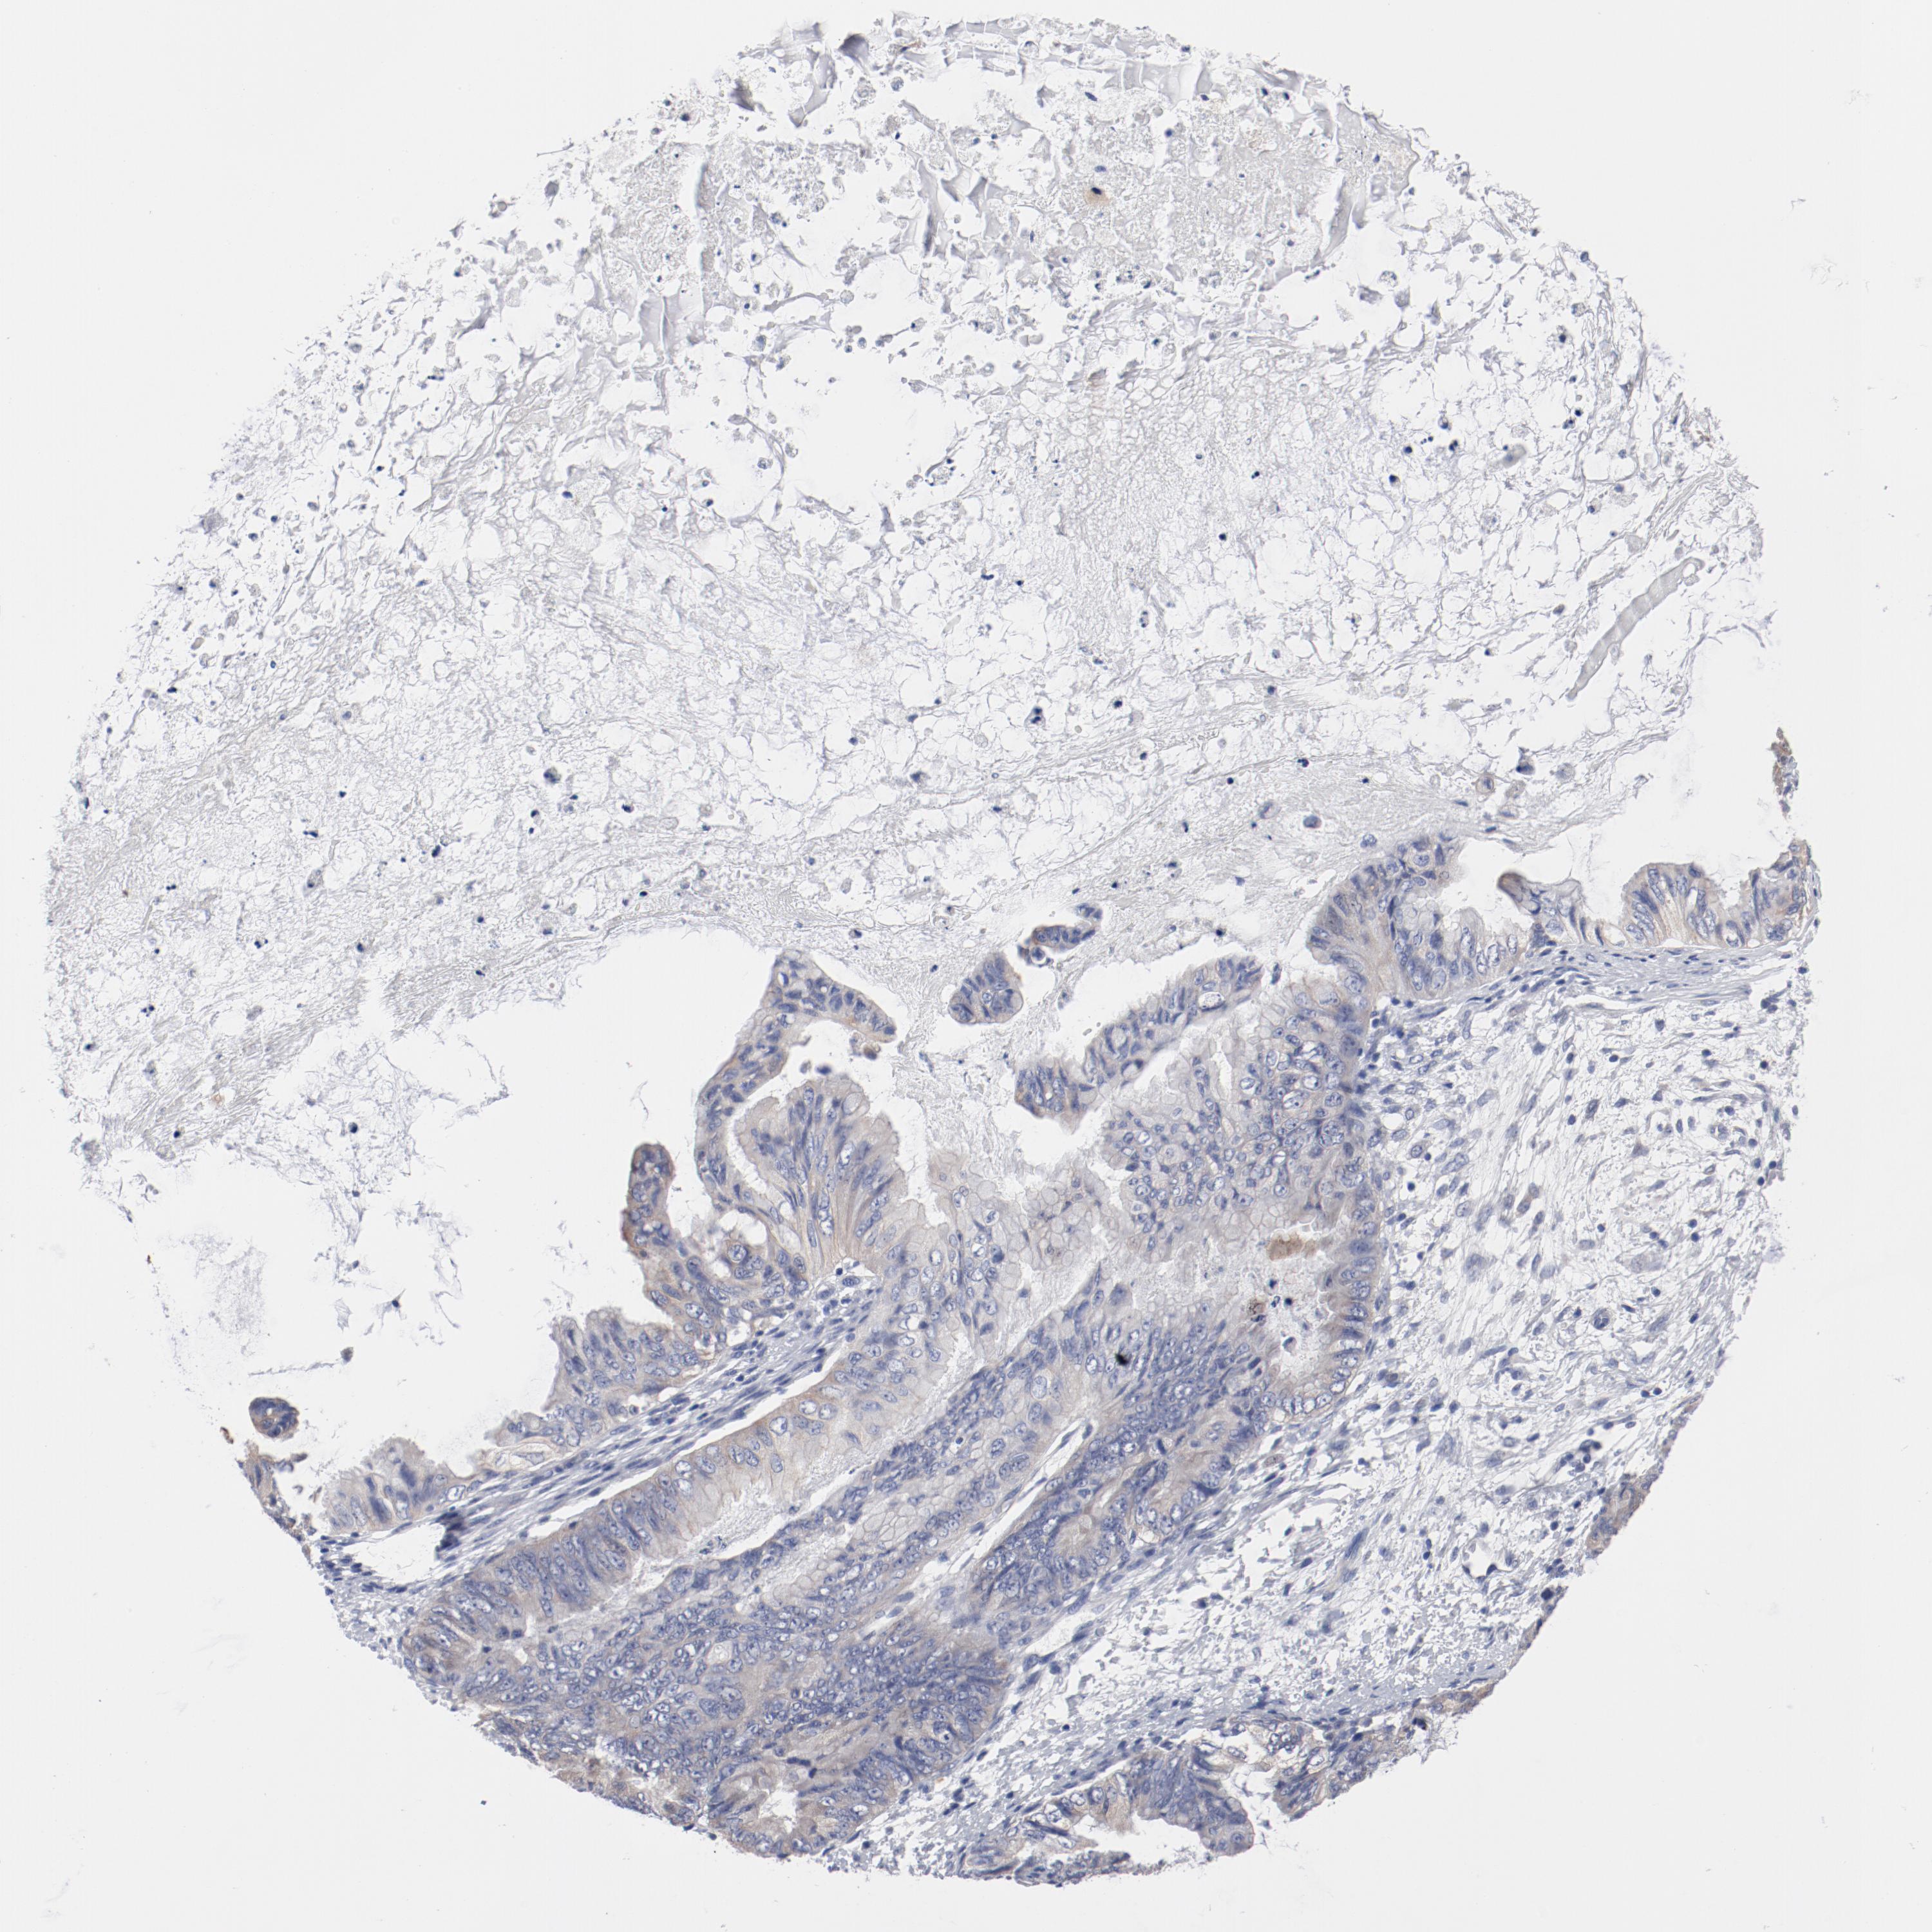

OVARIAN CANCER - Protein expressioni

A mouse-over function shows sample information and annotation data. Click on an image to view it in a full screen mode. Samples can be filtered based on level of antibody staining by selecting one or several of the following categories: high, medium, low and not detected. The assay and annotation is described here.

Note that samples used for immunohistochemistry by the Human Protein Atlas do not correspond to samples in the TCGA dataset.

Antibody stainingi

Antibody staining in the annotated cell types in the current human tissue is reported as not detected, low, medium, or high, based on conventional immunohistochemistry profiling in selected tissues. This score is based on the combination of the staining intensity and fraction of stained cells.

Each image is clickable and will lead to virtual microscopy that enables deeper exploration of all samples and also displays staining intensity scores, fraction scores and subcellular localization as well as patient and tissue information for each sample.

Antibody HPA003648

Cystadenocarcinoma, serous, NOS

Cystadenocarcinoma, mucinous, NOS

Carcinoma, endometroid